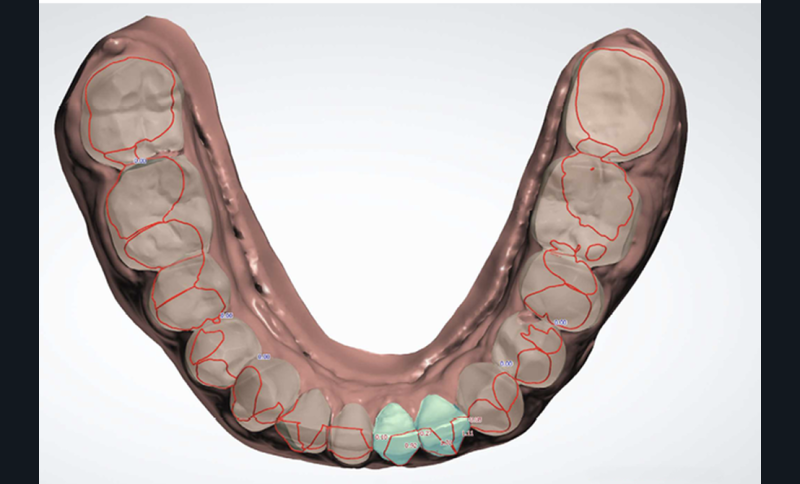

Plan de traitement

(fig. 4 à 10)

Le plan de traitement établi conjointement avec son chirurgien-dentiste traitant consiste à réaliser un alignement dentaire mandibulaire et à réaliser des extractions de 16 et 15 pour un remplacement par prothèse implanto-portée.

La durée orthodontique prévue est de neuf mois, avec comme contrainte principale l’absence de possibilités de modification des formes d’arcades.

Le gain de place se fera par des réductions interproximales sur la zone incisivo-canine mandibulaire.

Il est décidé de ne pas redresser la 43 complètement afin de ne pas entraîner d’interférences occlusales.

Un accompagnement par des meulages occlusaux est réalisé.